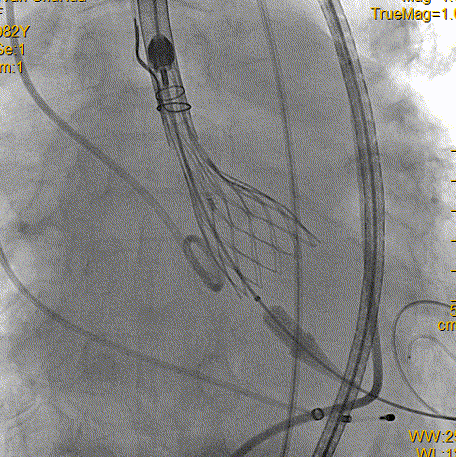

术中过程

右侧股动脉造影

左侧股动脉造影

输送系统定位

瓣膜释放